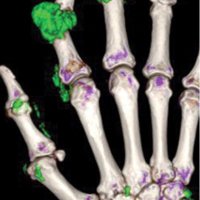

Acute gouty arthritis of the first metatarsophalangeal joint, termed “podagra,” was first identified by Egyptians in 2640 B.C. and continues to be a medical health problem today. The hallmark of gout is hyperuricemia with subsequent deposition of monosodium urate (MSU) crystals, which leads to inflammation and symptoms. Gout commonly involves specific joints and anatomic structures, and knowledge of these sites and imaging appearances are clues to the correct diagnosis.

Although diagnosing gout generally is straightforward, atypical disease may present a challenge if it is associated with unusual symptoms or sites, discordant serum urate level, or mimics of gout. Dual-energy computed tomography (CT) may be used to differentiate urate crystals from calcium by using specific attenuation characteristics, which may help diagnose gout. In patients with known tophaceous gout, dual-energy CT may be used for serial volumetric quantification of subclinical tophi to evaluate response to treatment.

Dual-energy CT can quantitatively identify monosodium urate crystal deposits with high sensitivity and specificity within joints, tendons, and periarticular soft tissues.

Given the utility of dual-energy CT in challenging cases and its ability to provide an objective outcomes measure in patients with tophaceous gout, dual-energy CT promises to be a unique and clinically relevant modality in the diagnosis and management of gout.